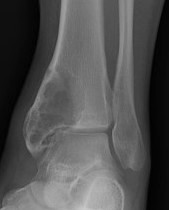

X-ray

Multi-loculated expansile lesion with cortical thickening

Often fail to make definitive diagnosis on xray